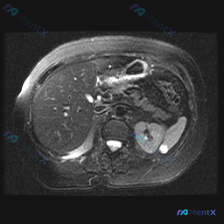

今天看到一份腹部MRI的T2WI图像,焦点在脾脏,整理一下读片的思考过程,避免踩坑。 先看核心影像表现 这是一张轴位T2WI,最突出的异常在脾脏: - 信号:脾实质内有数个类圆形极高信号影,信号强度接近脑脊液,提示是液体(浆液性为主)。 - 形态:边界清晰,但边缘呈分叶状,囊腔之间相互融合或紧邻,不...

看到一份挺有意思的影像分析申请,说是“脾脏病变”,但仔细理了理图像和逻辑,发现这里其实藏着一个经典的读片陷阱。整理一下思路和大家分享。 先看“原料”:图像的基本信息 这是一幅腹部MRI轴位图像。首先得先明确序列——这点其实挺关键的:图像里胆囊、肾盂、肠管内的液体都是明亮的高信号,肝脏、肾皮质这些实质...